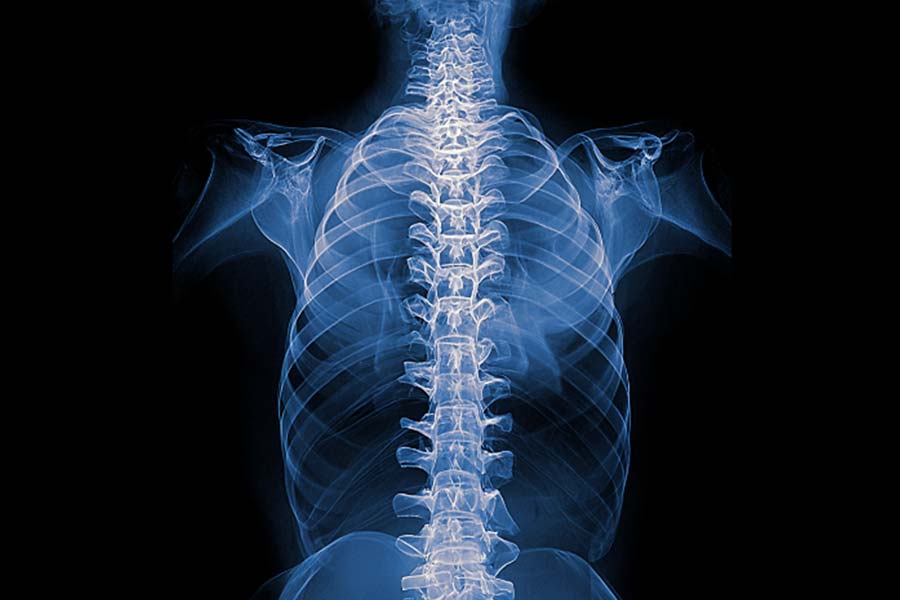

Radikulopatia odnosi się do uszkodzenia lub podrażnienia korzeni nerwowych nerwów rdzeniowych w obrębie kręgosłupa. Najczęściej spotyka się radikulopatię lędźwiową oraz szyjną.

Wraz z postępem choroby zwyrodnieniowej dochodzi do zwężenia przestrzeni międzykręgowej, zniekształcenia powierzchni trzonów, przemieszczenia powierzchni stawowych, a w konsekwencji zniekształcenia otworów międzykręgowych.

W związku z faktem, że korzenie nerwów rdzeniowych, przebiegające w bezpośrednim sąsiedztwie krążków międzykręgowych, wydostają się z kręgosłupa przez wąskie otwory międzykręgowe, nawet najmniejsza deformacja w przebiegu zmian zwyrodnieniowych może powodować nasilone dolegliwości.

Podstawą diagnostyki jest badanie MR, które jest bardzo dokładnie i umożliwia identyfikację nieprawidłowości mogących być przyczyną dolegliwości. Scyntygrafia oraz badanie RTG są polecane w razie podejrzenia złamania lub patologii kostnych.